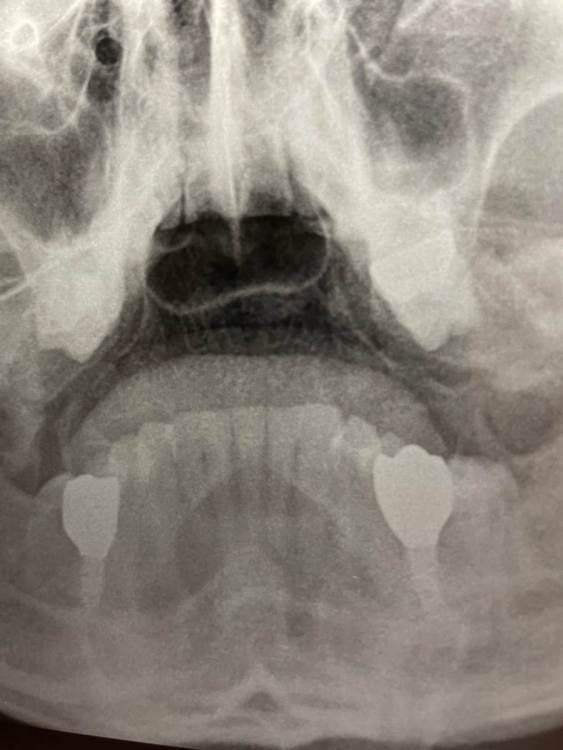

beetlea Опубликовано 7 сентября, 2023 Автор Поделиться Опубликовано 7 сентября, 2023 Есть снимок от Лора. Внизу это цирконий, а на верху справа металлокерамика Ссылка на комментарий